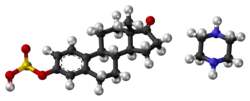

| Formula | C22H32N2O5S |

| Molar mass | 436.57 g·mol−1 |

| 3D model (JSmol) | |